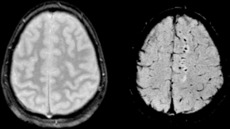

Compare SWI and GRE Trauma.png

Two MRI images of a patient with diffuse axonal injury resulting from trauma, at 1.5 tesla field strength. Left: conventional gradient recalled echo (GRE). Right: Susceptibility weighted image (SWI).